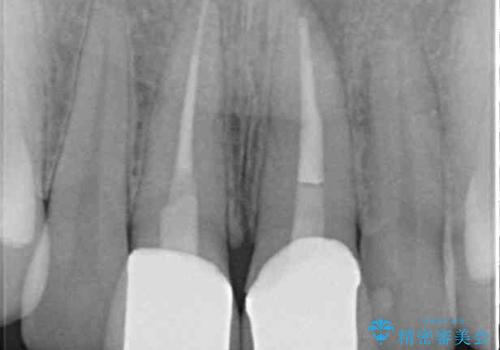

レントゲン写真より、変色してしまった歯は根管治療がされていなかったため、根管治療後にファイバーコアによる土台築製を行い、前歯2本をオールセラミッククラウンにて補綴することとしました。